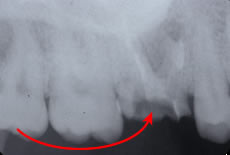

![]() |

保存不可能な歯の2つ後ろに使ってない親知らずの歯があります。 |